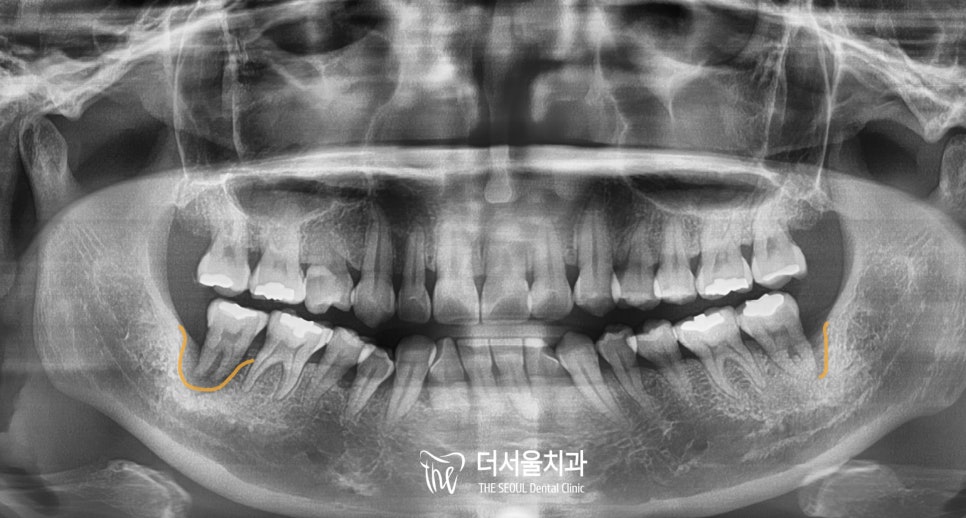

파노라마 엑스레이를 보면

양쪽 어금니 주변이 어둡게 보이는데,

이곳에 염증이 생겨서

치아를 감싸고 있는 잇몸뼈가 녹아내린 상황이였죠.

양쪽 어금니모두 상태가 좋지 않아서

심각한 부위부터 치료를 시작하기로 했는데,

오른쪽 큰 어금니가 ‘더’ 안좋아서

먼저 하기로 했습니다.